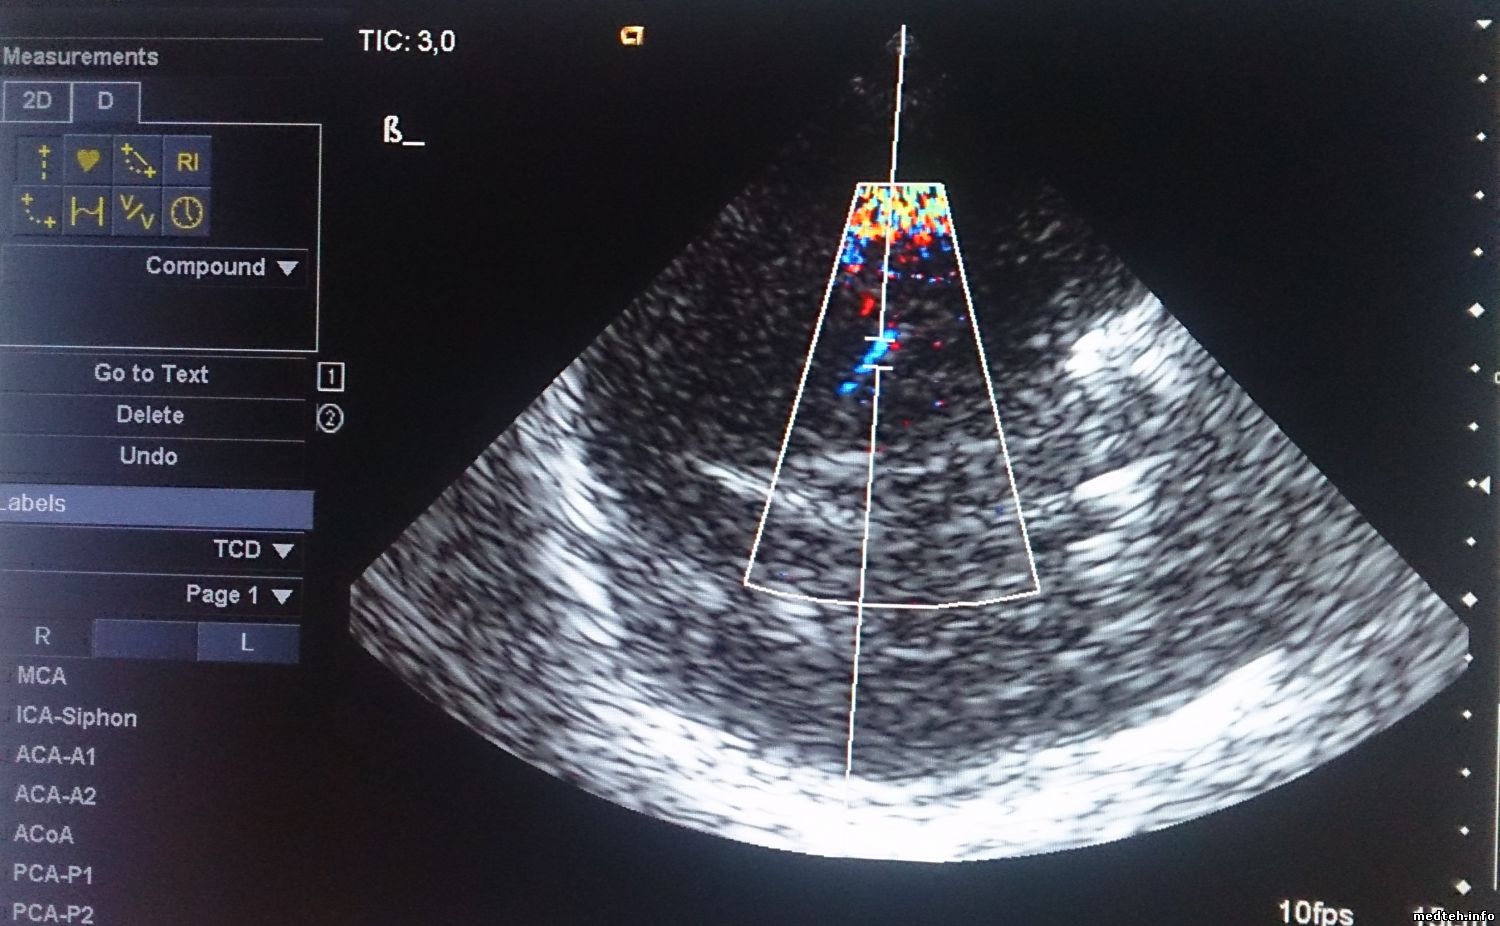

Сразу после включения качество более-менее (рис.1), хотя заметно, что изображение немного "восковое". К концу рабочего дня изображение ухудшается, повышается шум, изображение "плывет" (рис.2,3). На всех датчиках, хуже всего на фазированном. Появилось это давно. Аппарат ремонтировали по гарантии несколько лет назад, что-то меняли. Делали-ли tune-up, неизвестно. Пароля, естественно, нет. Как проконтролировать напряжения? Какие тесты можно сделать?